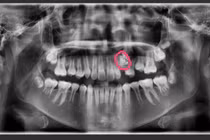

Sau khi khám và phân tích tổng thể, bác sĩ Kang cho biết tình trạng u xơ tử cung của Wang rất nghiêm trọng, không loại trừ khả năng u xơ tử cung lan tỏa. Có đến hơn 180 khối u trú ngụ trong tử cung và cách tốt nhất là cắt bỏ khu vực này.

Dù chuẩn bị kỹ lưỡng song quá trình phẫu thuật vô cùng khó khăn. Do có nhiều khối u ở vùng chậu, ổ bụng nên việc ekip phải tập trung cao độ. May mắn thay sau nhiều giờ chiến đấu, ca phẫu thuật thành công. Hơn 180 khối u với nhiều kích cỡ đã được lấy ra. Trong đó, khối lớn nhất có kích thước bằng nắm tay nam giới trưởng thành khiến bác sĩ nhiều năm kinh nghiệm như Kang cũng phải kinh ngạc.